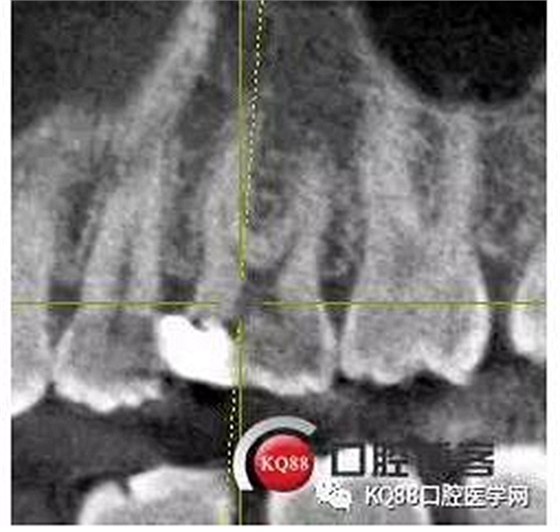

這兩張角度的截圖告訴我們這個牙齒一個典型的Y型根管,髓腔非常巨大,從根管口看,貌似一個根管口,但是根管銼下去以后,會兩個方向角度的分開。因?yàn)槲覀儸F(xiàn)在都是常規(guī)的機(jī)擴(kuò)與熱牙膠充填,建立直線根管口的暴露就變得非常重要,必須直線視野下操作,機(jī)擴(kuò)才不會發(fā)生扭曲折斷。目前市面上的根管銼有很多,M3,S3等,而此次我使用的是歐羅德卡PLEX軟銼,因?yàn)槭强谇?8贈送我的,所以我就先嘗試的使用了一下,我不會單方面的去評價(jià)比別的好,我覺得預(yù)備方法對了,都會很不錯,只能說一句這個用起來軟銼對后牙的預(yù)備確實(shí)不錯。根管預(yù)備,常規(guī)我都會先C銼疏通,如果直接15號很有可能會在根尖方形成臺階,以后就很難再下去了,當(dāng)C銼到達(dá)根尖孔后,予以初步測量長度,在用疏通機(jī)擴(kuò)針通入,然后一步步規(guī)范化開始,逐級預(yù)備,一個簡單的經(jīng)驗(yàn),如果當(dāng)使用的銼不容易到達(dá)根尖時,不要著急,用上一號,繼續(xù),再回來,就可以了,不然形成臺階,就很難操作了,常有人會覺得擴(kuò)根時,突然發(fā)現(xiàn),下不去了,排除斷針的可能性的話,臺階是最重要的,擴(kuò)根時,1%次氯酸鈉變沖洗,變預(yù)備,防止碎屑推出根尖孔,我沖洗常使用1%次氯酸鈉與蒸餾水,再充填前,會使用EDTA沖洗液去除根管壁油污。

一個上6,常規(guī)的拍片,同上面的方法,根管口定位,乍一看三個根管,但是仔細(xì)研究,發(fā)現(xiàn)近中頰根,兩個根管口的C型根管,心理明了以后開始常規(guī)操作。